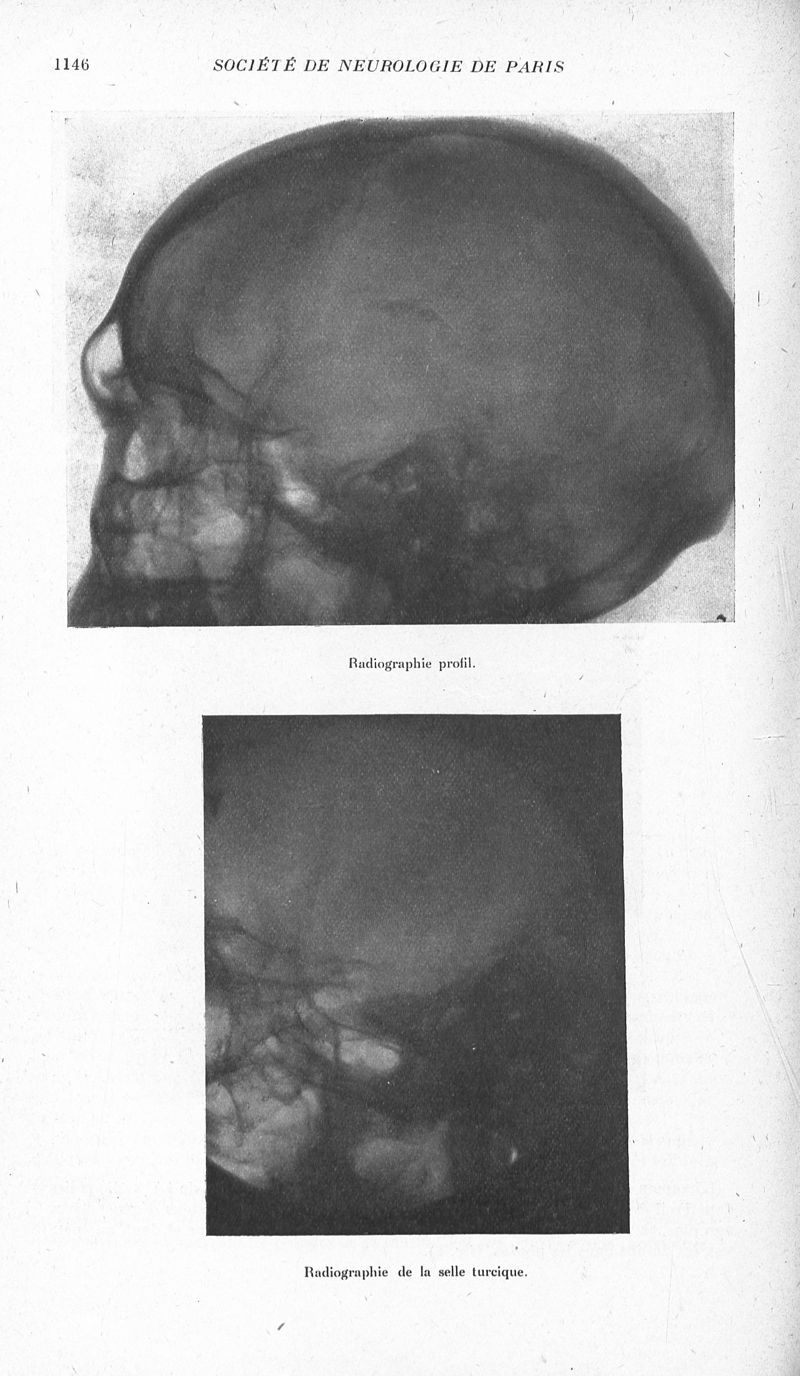

Revue neurologique

1933, vol 1. - Paris : Masson , 1933.